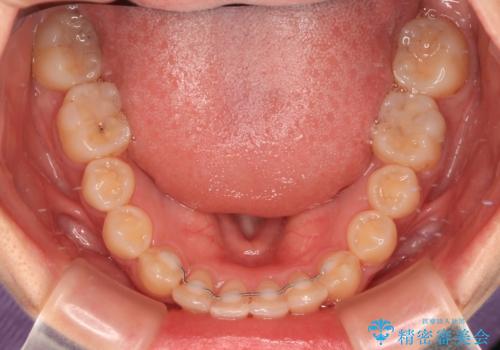

深い咬み合わせとデコボコの歯列をワイヤー矯正で改善

- 前歯のデコボコと深い咬み合わせを改善したいとのことで来院された患者様です。

奥歯の咬み合わせは上顎に対して下顎が後方位にあり、上顎前歯で下顎前歯が隠れるような典型的な過蓋咬合です。

補助装置を用いて上顎大臼歯を後方に移動させながら、ワイヤー装置で歯列を整えて深い咬み合わせを挙上することとしました。

下顎の装置が頻繁に脱落し、治療は難航しましたが、当初予定の2年間で無事に治療を終えることができました。